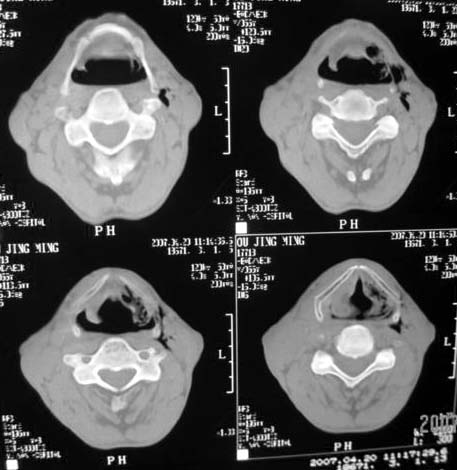

以下是引用dyqct在2007-4-20 16:19:00的发言:[br]考虑:1、左侧梨状窝区破裂伴左颈深、浅部气肿。[br] 2、右侧甲状腺区血肿(请追问病史是否伤及右颈部)。[br] 3、建议病情稳定后增强扫描除外右侧甲状腺腺瘤。